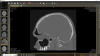

Fig 4. One-year recall CBCT. Note resolution of prior periapical pathology on tooth No. 13, sinus communication, and MSEO.

Figure 4

Periapical and CBCT imaging confirmed the presence of apical pathology, as well as a dramatic sinus communication with MSEO (Figure 1 and Figure 2). The diagnosis for tooth No. 13 was pulpal necrosis with asymptomatic apical periodontitis. NSRCT was completed (Figure 3). At the patient's 1-year follow-up appointment, tooth No. 13 remained asymptomatic, her sinusitis was resolved, and complete radiographic healing of both periapical pathology and the MSEO was noted (Figure 4).

Both of these cases illustrate the improvement in sinus pathology findings from preoperative CBCT scans to postoperative recall CBCT scans following NSRCT (Figure 4, Figure 10, and Figure 11). In addition, in both instances the re-establishment of the previously obliterated cortical boundary between the apex and maxillary sinus was impressive. Clinically, the resolution of sinusitis symptoms in both patients after receiving nonsurgical endodontic therapy was quite notable. Despite the absence of specific dental pain, these patients' sinusitis symptoms could not have been alleviated without the endodontic interventions due to the odontogenic etiology of their disease. These two cases demonstrate the pivotal role of CBCT imaging in diagnosis and recall as well as the success of NSRCT when treating cases of MSEO.